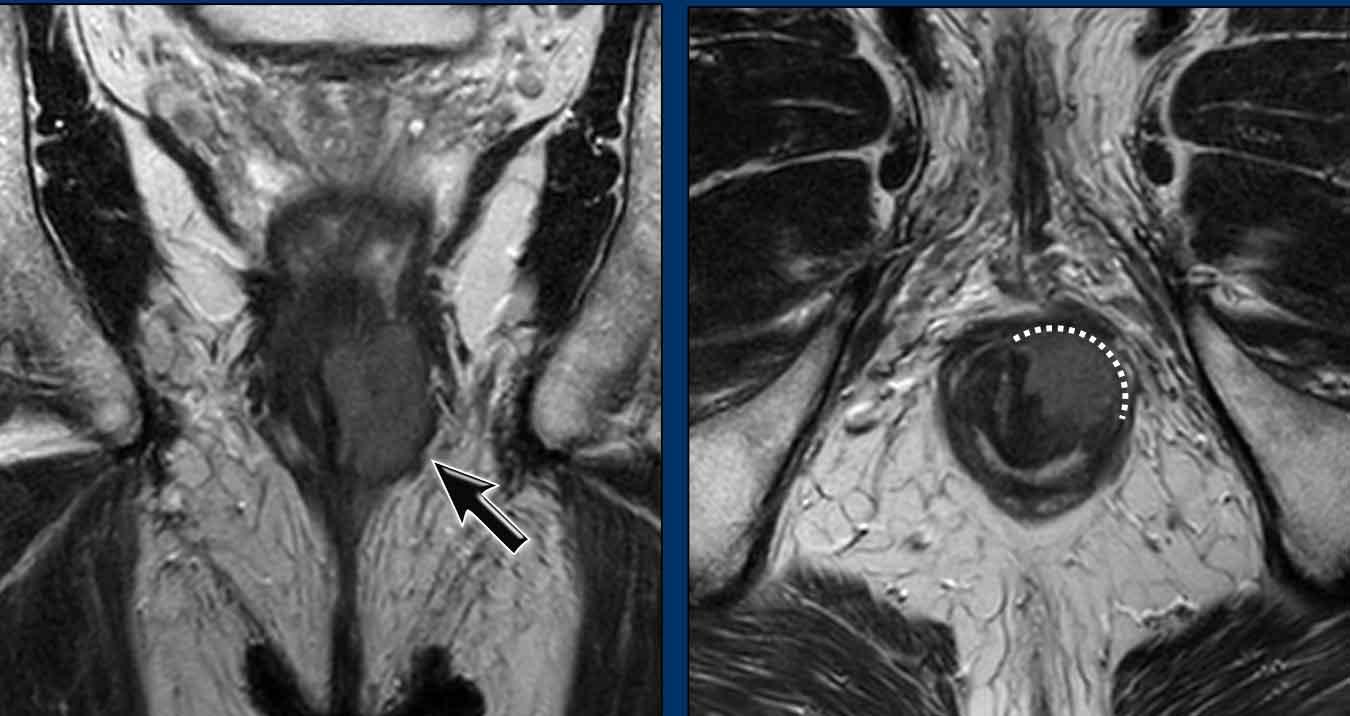

Hình ảnh

Một ví dụ khác cho thấy khối u xâm lấn ½ trên của ống hậu môn.

Khối u xâm lấn cơ thắt trong, khoang liên cơ thắt và cơ thắt ngoài từ 7-10 giờ.

Khối u xâm lấn cơ mu-trực tràng và cơ nâng hậu môn bên phải (mũi tên) và lan rộng vừa qua mức chỗ nối hậu môn-trực tràng (đường chấm) vào đoạn xa trực tràng.

Khối u (mũi tên) trước điều trị kèm hạch mạc treo trực tràng nghi ngờ.

Giai đoạn: cT2N1a.